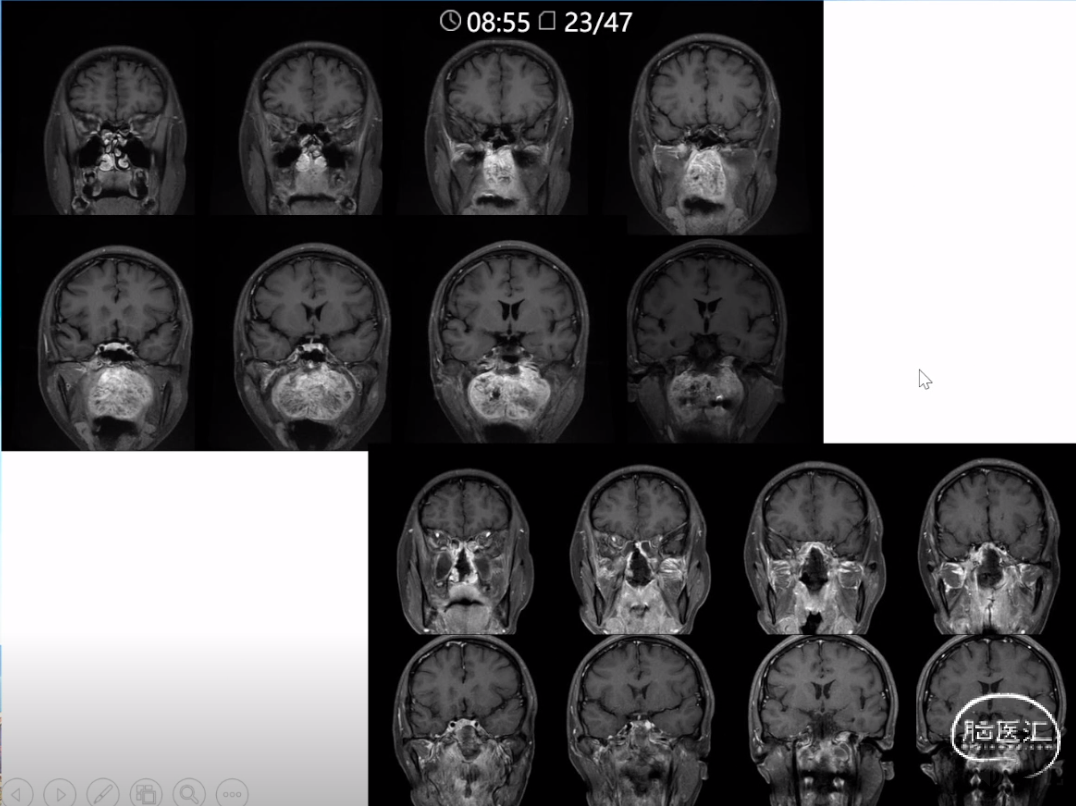

本文主要内容为:脊索瘤临床特点、治疗选择,以及多个手术病例。